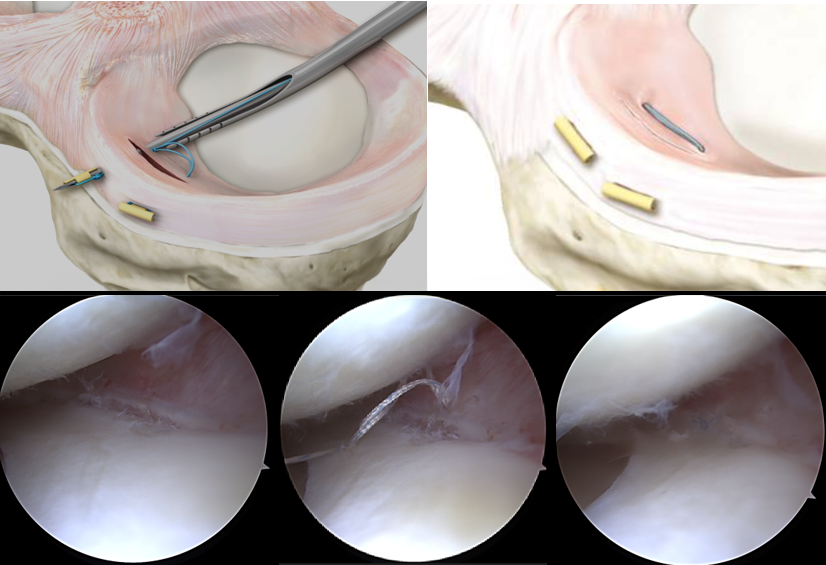

B) Meniskusnaht – den Meniskus erhalten statt entfernen

Die Meniskusnaht ist ein arthroskopisches, gelenkerhaltendes Verfahren, bei dem der eingerissene Meniskusanteil mit feinen Nahttechniken fixiert wird. Ziel ist es, den Meniskus in seiner ursprünglichen Form zu rekonstruieren, damit er seine wichtige Funktion als Stoßdämpfer und Gelenkstabilisator weiterhin erfüllen kann.

Studien zeigen: Schon eine geringe Entfernung von Meniskusgewebe kann die Belastung auf den Gelenkknorpel deutlich erhöhen – und so das Risiko für eine frühzeitige Arthrose steigern.

Daher ist die Meniskusnaht vor allem bei frischen Rissen in der gut durchbluteten Zone des Meniskus eine sehr sinnvolle Option – dort, wo die Heilungschancen am höchsten sind.

Voraussetzungen für eine erfolgreiche Meniskusnaht:

• Ausreichende Durchblutung im Bereich des Risses

• Stabile Bandverhältnisse im Kniegelenk

• Gerade Beinachse, um die Heilung nicht zu gefährden

Meniskusnaht